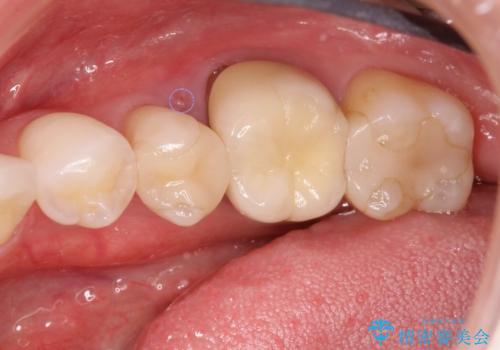

放置された虫歯 小矯正+歯周外科による保存処置